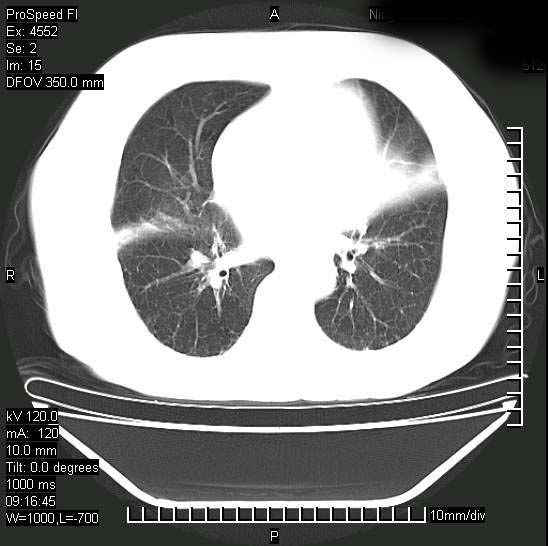

短短几天内,病变范围明显增多扩大,以左侧明显,而且双侧出现胸水,还是考虑感染.

短短几天内,病变范围明显增多扩大,以左侧明显,而且双侧出现胸水,我更多考虑左侧中心性肺癌并并阻塞性不张及肺炎,炎症变化也太快了!

无论是肿瘤还是炎症4天的时间都发展够快的,并且还在治疗中,如果说是左肺癌那么右肺的病变不好解释,本人更加倾向于炎症,左肺舌叶支气管被痰栓或血凝块堵塞,造成阻塞性肺炎。

1)两肺结核并感染。2)不排除左肺上叶中央型肺癌并阻塞性肺炎、肺不张可能;建议行纤支镜检查。3)右肺门及纵隔淋巴结肿大。4)双侧胸腔积液。

陈旧性肺结核及左下肺不张,咯血后肺部感染,双胸腔积液,高热可能与痰液引流不畅有关。